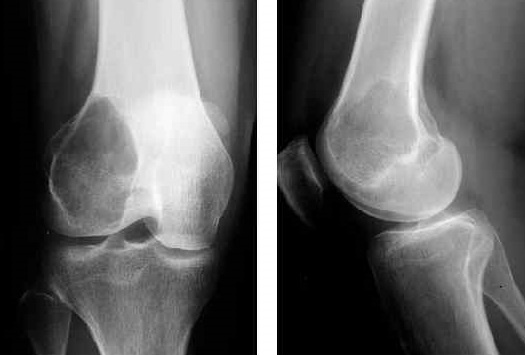

1. Рентгенография: Первое исследование для визуализации костной структуры.